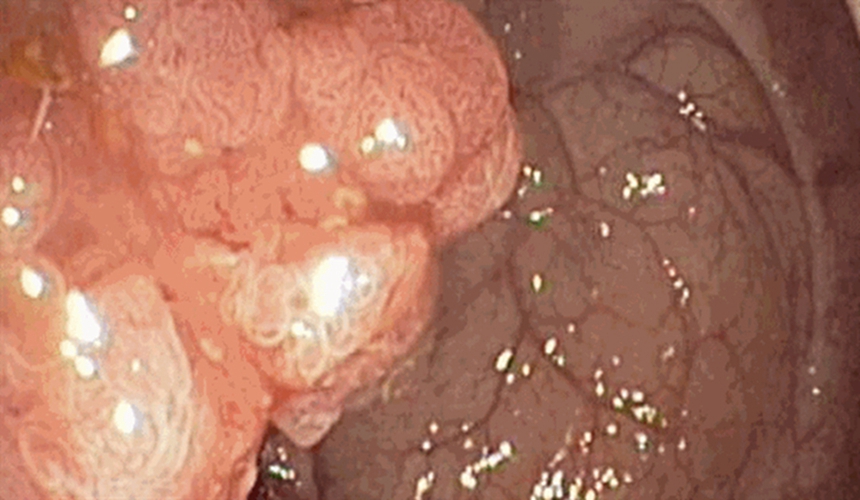

右半結腸癌腺癌

右半結腸癌腺癌一級

右半結腸癌的腺癌常見 臨床 特點

右半結腸癌的腺癌二級常見 臨床特點

右半結腸癌的腺癌一級常見 臨床特點